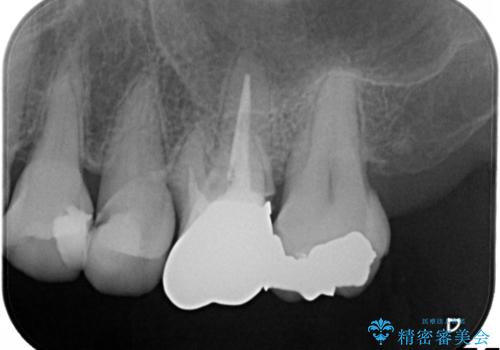

発見の難しい虫歯。根管治療から被せもの治療

- 定期検診にて被せものと歯との隙間に虫歯を発見した患者様です。

根管治療から被せもの治療(ベレッツァ)まで行いました。(根管治療は林院長に依頼)